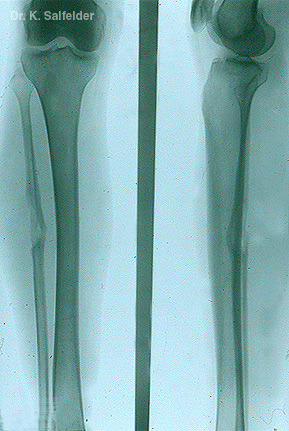

Abb. 18,24: Parakokzidioidomykose

Auch die Knochen bleiben bei der generalisierten Form dieser Pilzinfektion nicht verschont